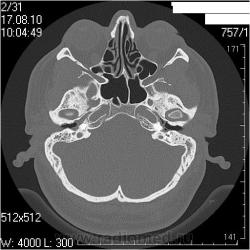

Правая височная кость

Наружный слуховой проход: конфигурация обычная, просвет не сужен, костные стенки ― ровные, четкие.

Сосцевидный отросток: тип строения склеротический, в сохранившихся ячейках отмечаются снижение прозрачности за счет патологических структур.

Воздушные полости среднего уха: пневматизация нарушена полностью за счет мягкотканных (41едН) патологических структур; размеры аттика, адитуса и антрума в пределах нормы. Ширина аттика ― 5,6мм (N=6.4-7мм), адитуса ― 2,1мм (N=3,1-3,3мм), антрума ― 4,6 мм.

Костное устье слуховой трубы: заполнено мягкотканными патологическими структурами.

Слуховые косточки прослеживаются

Внутреннее ухо: размер, форма, положение, плотность и контуры элементов структур внутреннего уха не изменены.

Внутренний слуховой проход: конфигурация не изменена, контуры ровные, четкие, ширина ― 3,2мм (N=4-6мм)

Левая височная кость

Наружный слуховой проход: конфигурация обычная, просвет не сужен, костные стенки ― ровные, четкие.

Сосцевидный отросток: тип строения склеротический.

Воздушные полости среднего уха: пневматизация нарушена за счет пристеночных мягкотканных (41едН) патологических структур; размеры аттика, адитуса и антрума в пределах нормы. Ширина аттика (на уровне латерального канала) ― 5,7мм (N=6.4-7мм), адитуса ― 3,5мм (N=3,1-3,3мм), антрума ― 6,4мм.

Костное устье слуховой трубы: пристеночные мягкотканные патологические структуры.

Слуховые косточки прослеживаются

Внутреннее ухо: размер, форма, положение, плотность и контуры элементов структур внутреннего уха не изменены.

Внутренний слуховой проход: конфигурация не изменена, контуры ровные, четкие, ширина ― 4,3мм (N=4-6мм)

Заключение: КТ- признаки двустороннего хронического среднего отита: склеротические изменения больше выражены в левом сосцевидном отростке; мягкотканные патологические структуры в воздушных полостях среднего уха больше выражены справа; блок костного устья правой слуховой трубы; неполный блок костного устья левой слуховой трубы